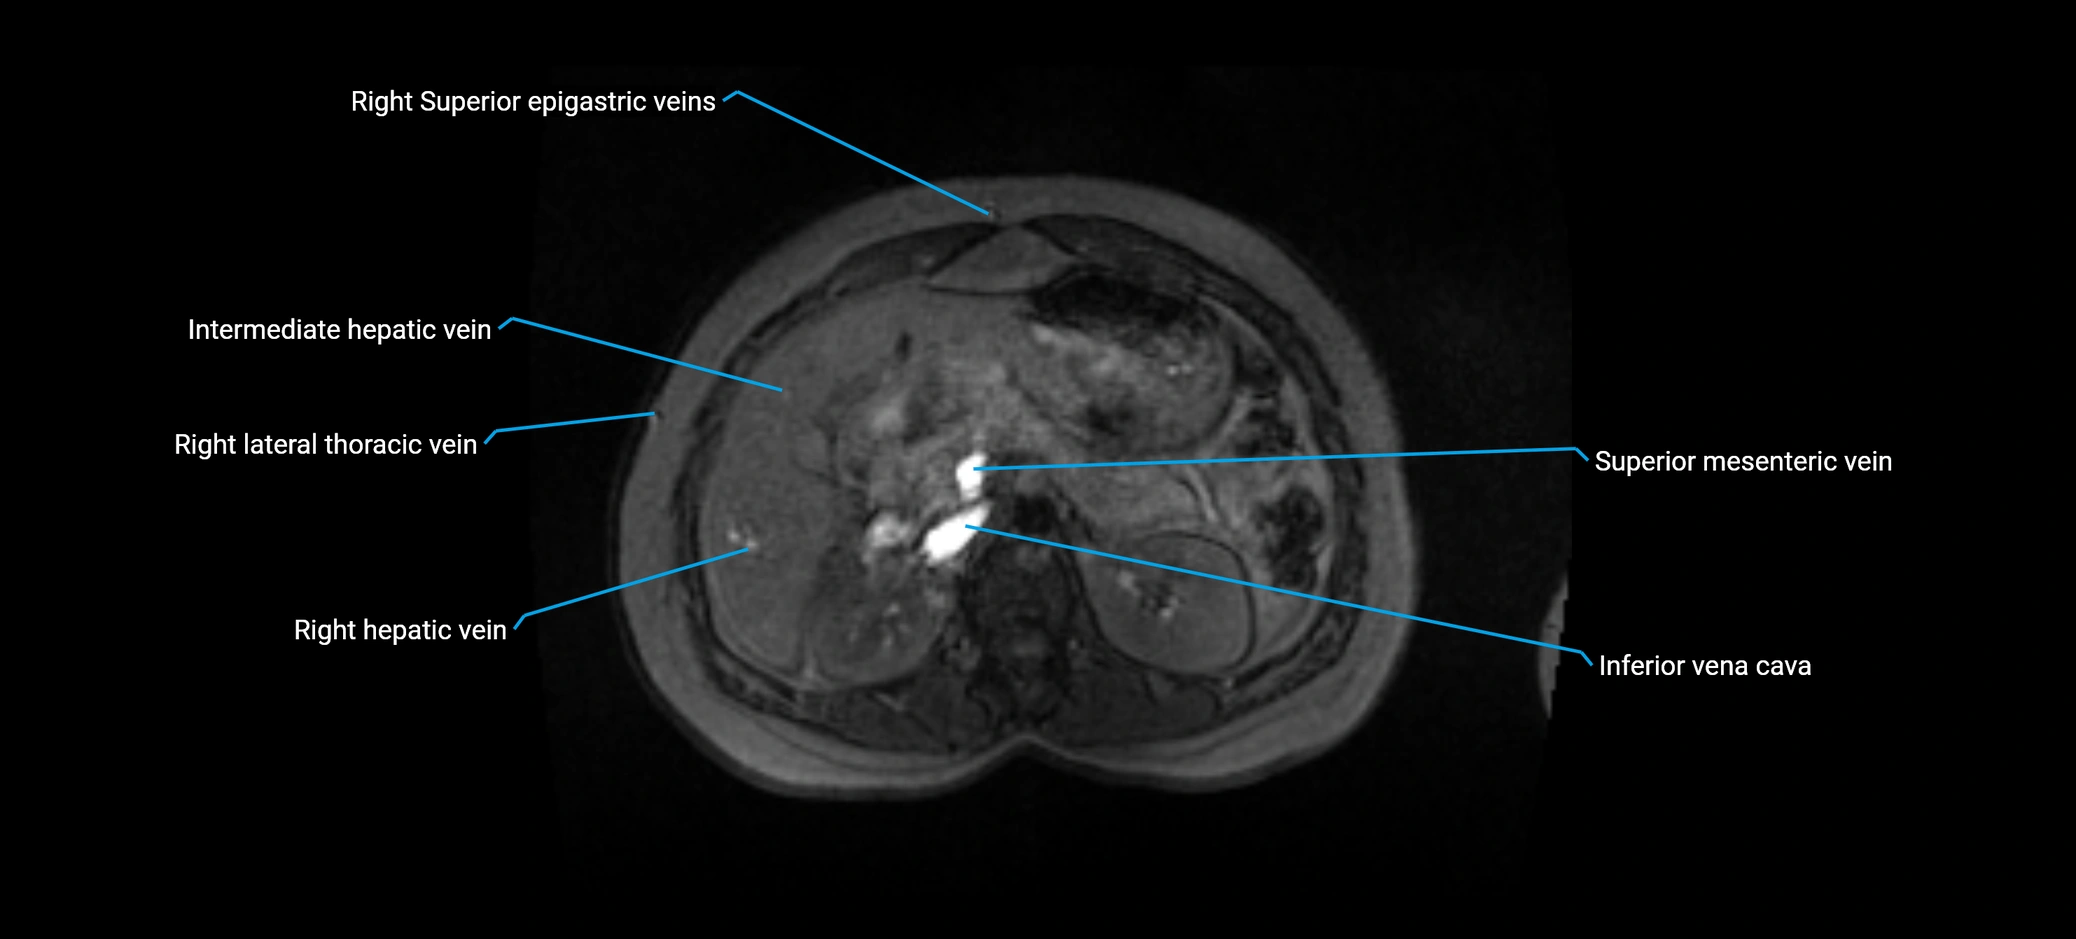

MRI image

image